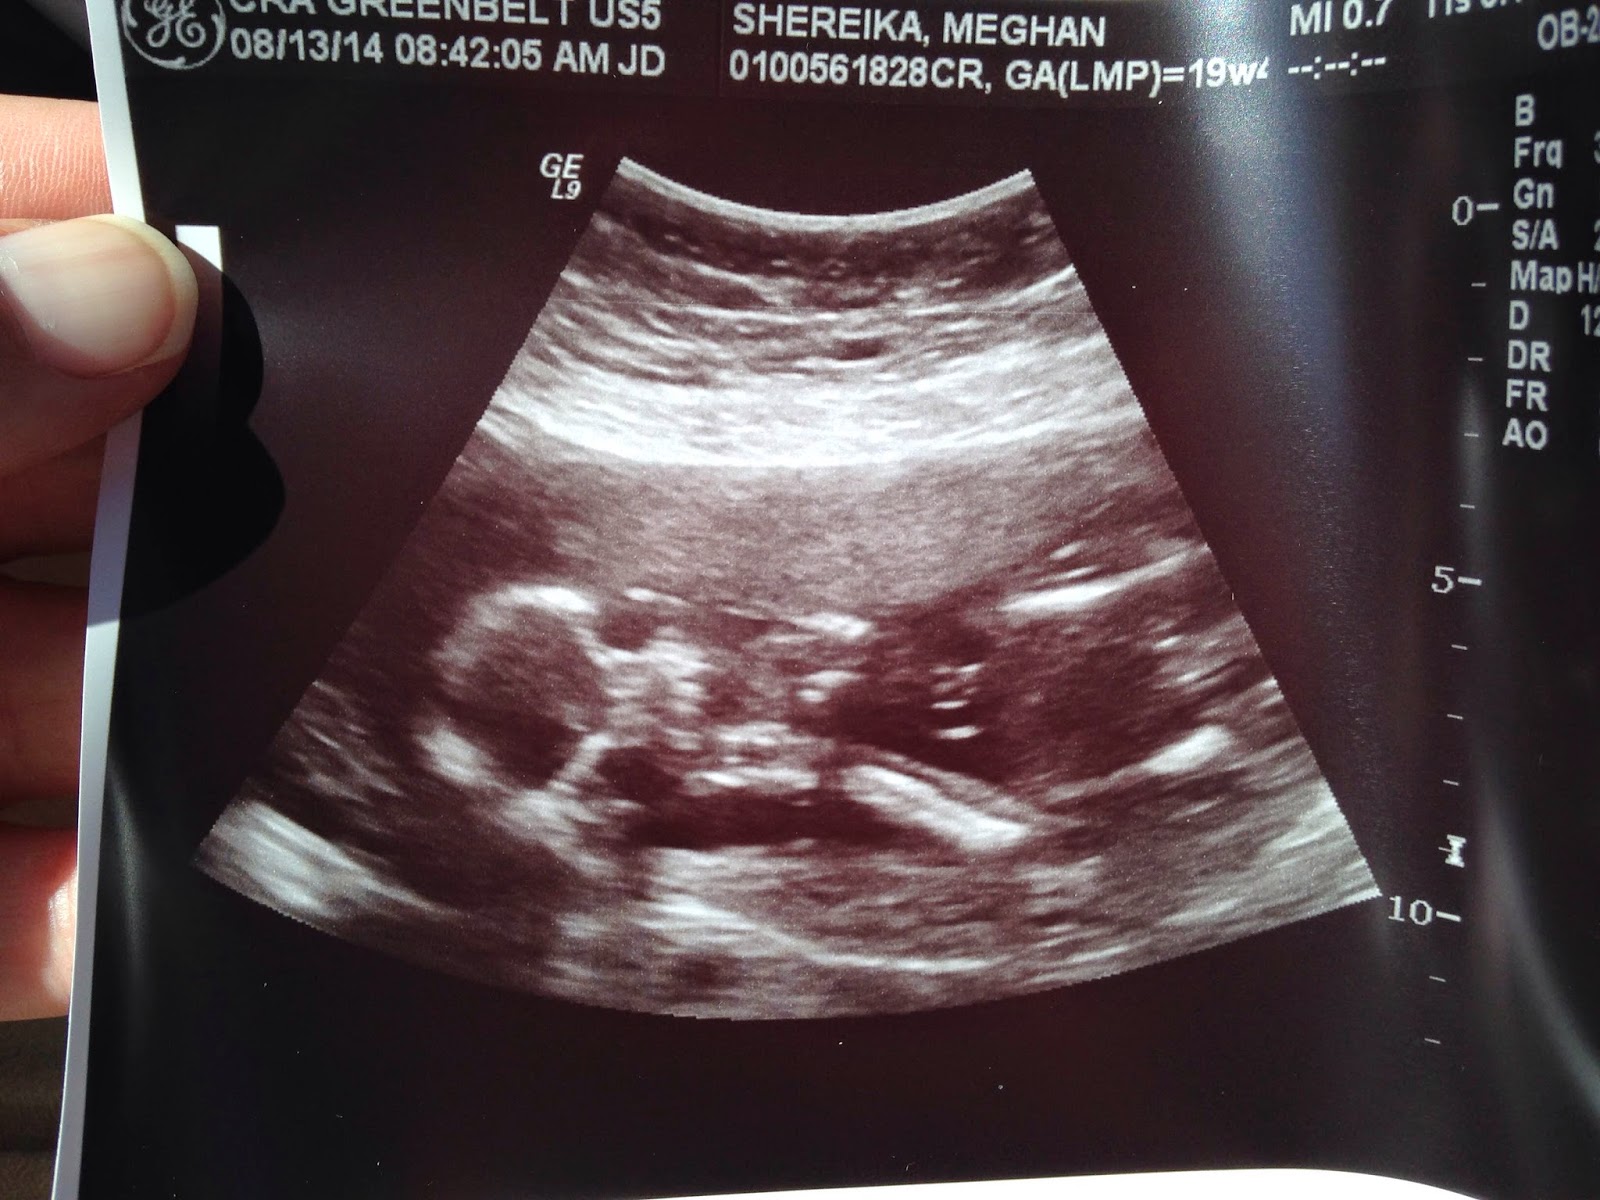

Ultrasound and 19 weeks

Last week we went in to have an ultrasound/anatomy scan. The ultrasound tech was very nice, and after a few minutes, she said that everything looked good, and that the baby is moving a lot!

She tried looking for clues to tell us if Baby Shereika is a boy or girl, but unfortunately, it's legs weren't cooperating.

We did get some nice pictures, though!

And the best one: face, hands, and legs, all in one!